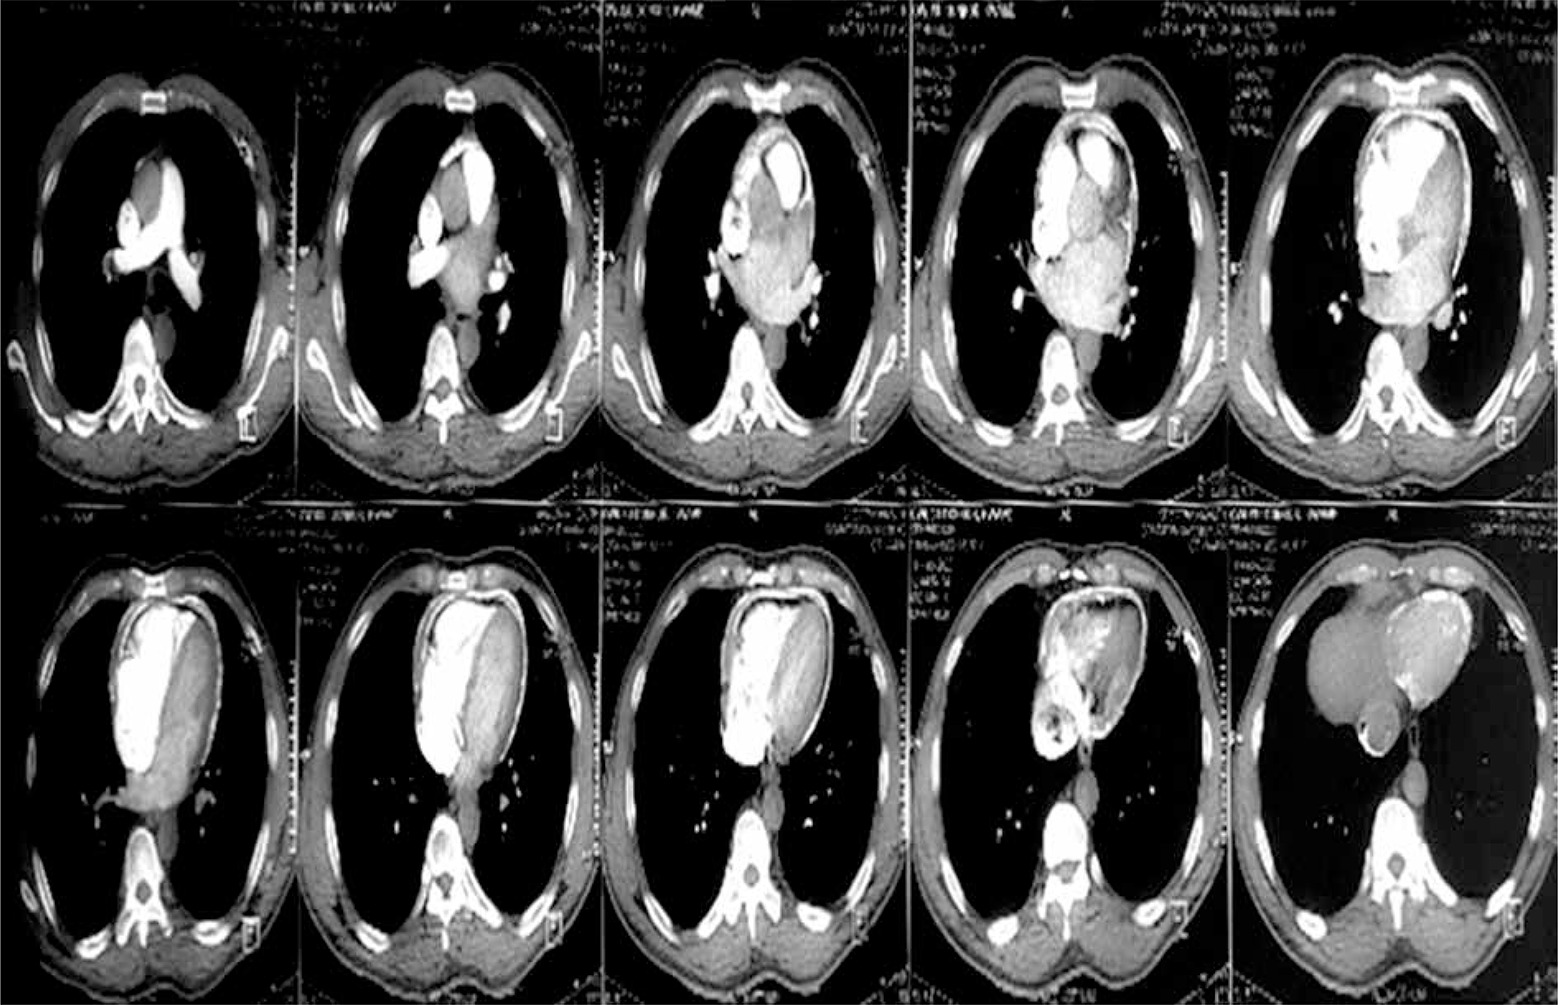

Figure 3

Computed tomography scan of one of the patients showing the calcification ring of calcific constrictive pericarditis

Chest X-ray in patients with constrictive pericarditis may show small or normal cardiac size but presence of cardiomegaly does not rule out constriction [7]. Presence of pericardial calcification – best seen on anterior, oblique or lateral views – is highly suggestive of chronic constrictive pericarditis [1]. However, it has been reported in less than 30% of surgically confirmed cases of constrictive pericarditis [11, 13, 16]. This is consistent with our current study where 2 (20%) out of the ten cases studied showed calcification on both the chest and CT scan, as shown in Figures 2 and 3. Far superior diagnostic yields are achieved with the use of echocardiogram, cardiac CT or magnetic resonance imaging (MRI) [13]. Cardiac CT scan or MRI provides a better assessment of pericardial thickness and calcifications and visualization of any abnormal ventricular contours caused by the constriction [11, 16]. Echocardiography features indicative of constrictive physiology include respiration-related ventricular septal shift, preserved or increased medial mitral annular e-velocity and prominent hepatic vein expiratory diastolic flow reversals [17]. Currently, the use of cardiac catheterization in the diagnosis of constrictive pericarditis is decreasing due to the increased diagnostic accuracy of echocardiography, CT scanning and MRI [13]. However, cardiac catheterization is the gold standard for diagnosis in the event of indeterminate findings with the non-invasive tests [11]. The current study employed two main modalities to confirm the diagnosis of constrictive pericarditis, namely chest CT scan and echocardiography with supporting evidence from chest X-ray and ECG. Six (60%) out of the 10 patients had ECG, 9 had chest X-ray, 8 had echocardiography and 4 had chest CT scan. Three (30%) had confirmation of the diagnosis from both echocardiography and chest CT scan, as shown in Table II.